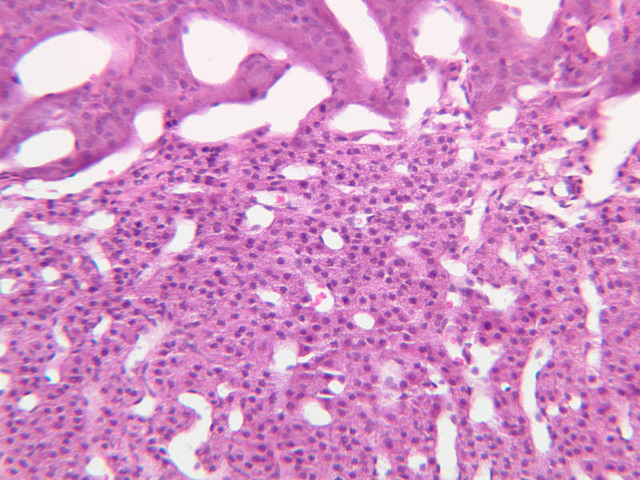

Examine slide B-56 (H&E [2.5x, 10x, 20x, 40x-labeled] [10x, 20x, 40x-labeled] [20x, 40x] [10x, 20x, 40x-labeled] [10x, 20x, 40x]). The connective tissue capsule of each parathyroid gland is continuous with that of the thyroid gland. It extends into the substance of the gland, dividing it into poorly defined lobules. Fat cells may separate the groups of cells and increase with age. Note the rich capillary network. The parenchyma is composed of two types of cells: (1) Principal or chief cells and (2) oxyphil cells. The polygonal chief cell is by far the more numerous cell type. Its nucleus is centrally located and has a vesicular chromatin pattern with a prominent nucleolus and its cytoplasm stains rather lightly. Oxyphil cells, which are less regular in shape and considerably larger than chief cells, are scattered singly or in small clusters. Their nuclei are smaller and more condensed than those of the chief cells and, owing to a very rich complement of mitochondria, their cytoplasm is distinctly acidophilic.